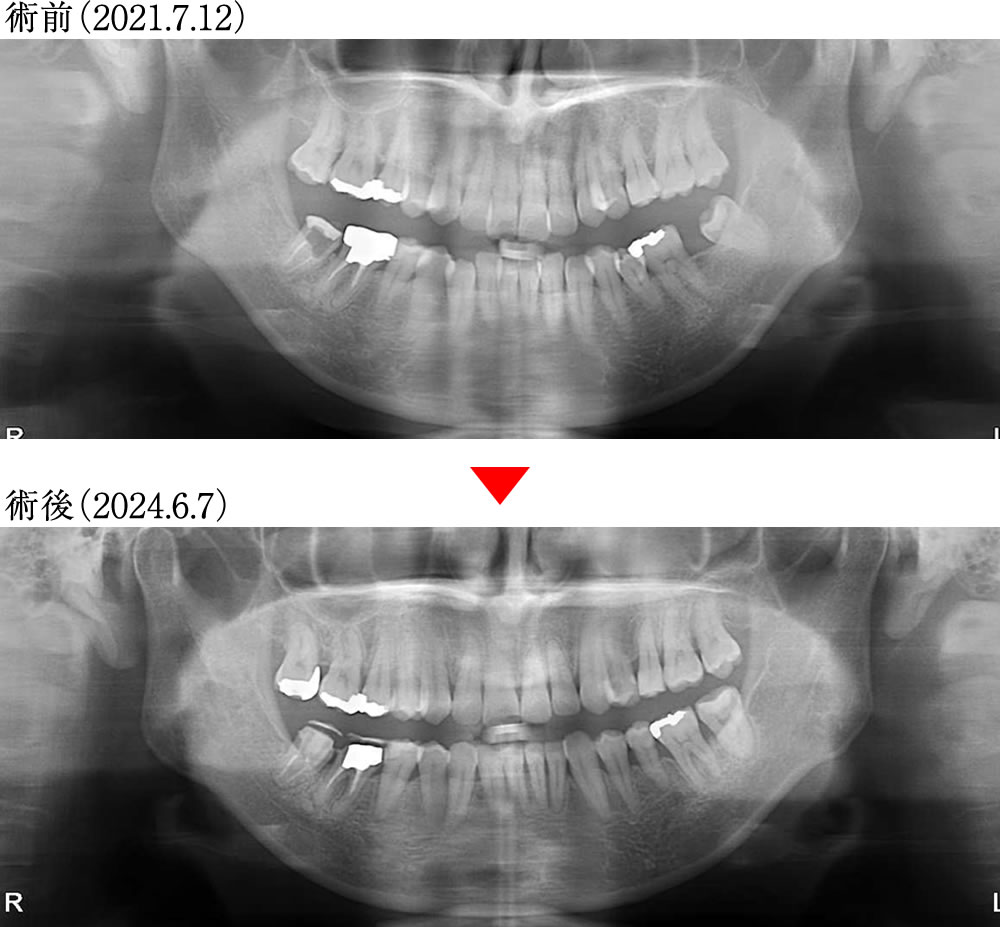

治療前後のレントゲン画像

術前は左下の奥歯が欠損している状態でしたが、親知らずを有効に活用することで、理想的な咬合構造で歯並びを再構築することができました。また、歯軸も整直され、機能的かつ安定した口腔環境が実現しました。